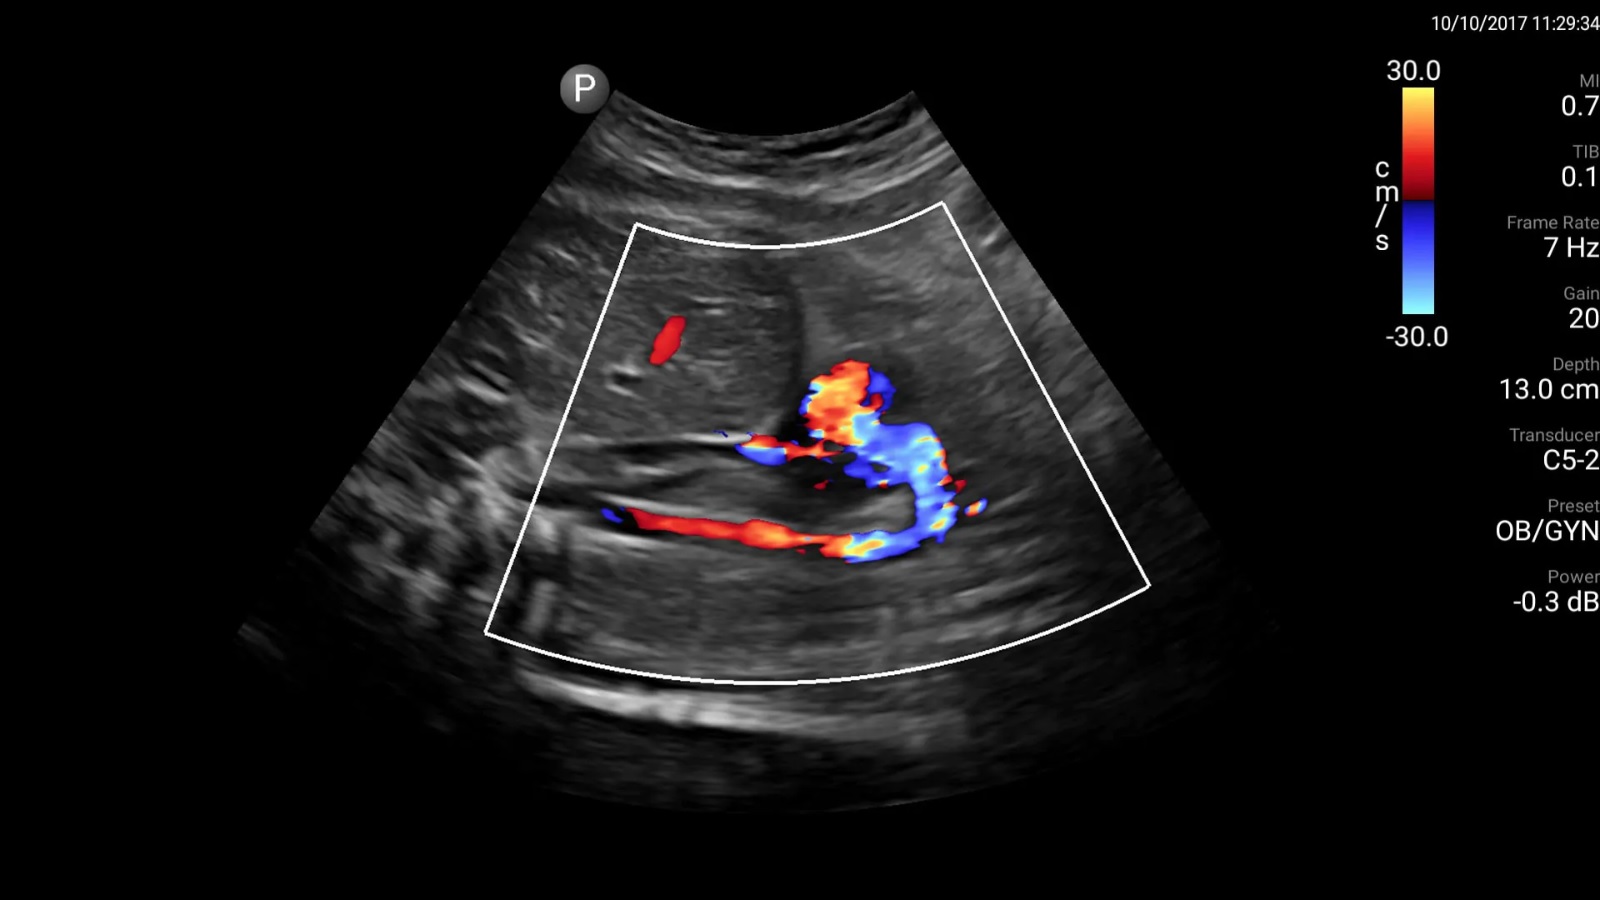

Dr Achyut Patil explains how the investigative test call Colour Doppler can help identify problems associated with the lower limbs. The Colour Doppler ultrasound is a non-invasive test. It estimates the...